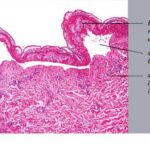

Histopathology. EM is considered the prototype of the vacuolar form of interface dermatitis . The early changes include vacuolization of the basal cell layer; tagging of lymphocytes along the dermal-epidermal junction; and a sparse, superficial, perivascular lymphoid infiltrate . Necrosis of individual keratinocytes in the basal unit occurs, which is the hallmark of EM. Because of its acute nature, there is an orthokeratotic stratum corneum. Mild spongiosis, papillary dermal edema, and extravasation of red blood cells are seen. As the lesion becomes more developed, there is a moderate lichenoid infiltrate of Iymphohistiocytes at the dermal-epidermal junction with exocytosis. More apoptotic keratinocytes within and above the basal epidermal layer are present. The |

intensity of epidermal necrosis varies from vacuolated individual keratinocytes surrounded by lymphocytes (satellite cell necrosis) at the basal unit to confluent necrosis in association with intraepidermal and subepidermal vesicles. The dermal infiltrate comprises lymphocytes and histiocytes. Eosinophils may also be present. Although one study has noted a significant number of eosinophils in drug-induced EM, this has not been noted by others. In the authors’ estimation, a generous number of eosinophils exclude EM. One study has found that an acrosyringium concentration of apoptotic keratinocytes in EM is a clue to a drug etiology . In early lesions of SJSITEN, apoptotic keratinocytes are observed scattered in the basal layer of the epidermis. In established lesions, there are numerous necrotic keratinocytes, even full-thickness epidermal necrosis, and a subepidermal bulla. The dermal inflammatory infiltrate is sparser in TEN than in EM (Fig. 9-278). Extravasated erythrocytes are commonly found within the blister cavity. Melanophages within the papillary dermis occur in late lesions. Eccrine epithelium shows a variety of changes from basal cell apoptosis to necrosis of the duct. |

In general, EM shows less epidermal necrosis, more dermal inflammation, and exocytosis, whereas SJS and TEN reveal more epidermal necrosis, less dermal inflammation, and exocytosis. However, due to the overlapping histologic features among EM, SJS, and TEN, histologic examination-while important for recognizing the spectrum of disorders-is not reliable for classifying the disease. Correlation with clinical presentation is essential. |